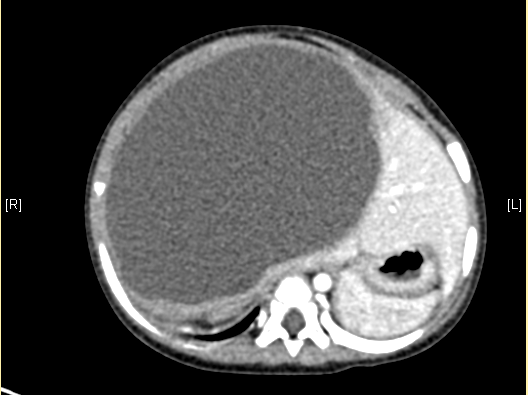

上腹部增强CT:肝右叶囊实性占位。上腹部增强CT示间叶性错构瘤。

术前CT检查:

动脉期

静脉期

平衡期